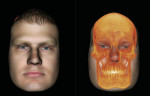

With 3D image data sets, small FOV images can be stitched together or two separate images can be superimposed to show a pre- and postoperative condition or simply a change in position, such as an open and closed TMJ view. It is also possible to take a conventional 2D digital photograph and identify enough points of reference with the 3D CBCT data set that the photograph can be superimposed over the bony structures to place the face of the patient over his or her hard tissues (Figure 9).